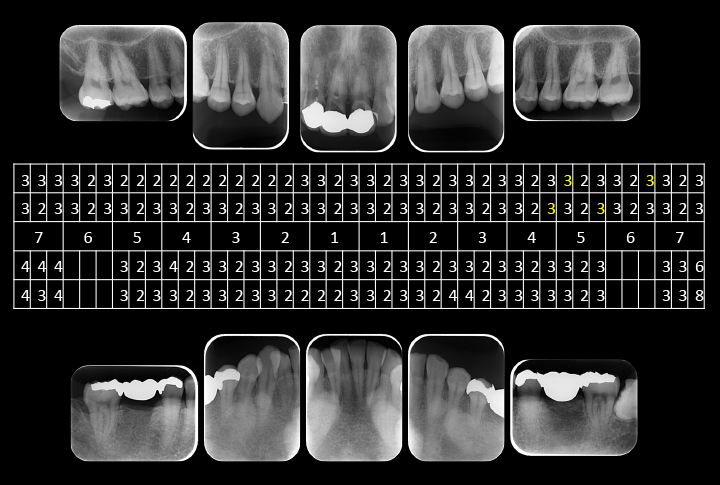

初診時口腔内写真5枚法

初診時口腔内写真五枚法です。

主訴である右上2~左上1は初診日に仮歯に置き換えてあります。

デンタル10枚法及びプロービングチャート

デンタル10枚法及びプロービングチャートです。

全体的には歯槽骨の吸収はみられませんが、左下7は左下8の影響により、遠心部に垂直性の骨欠損がみられます。

右上2から左上1には不十分な根管充填がみられます。